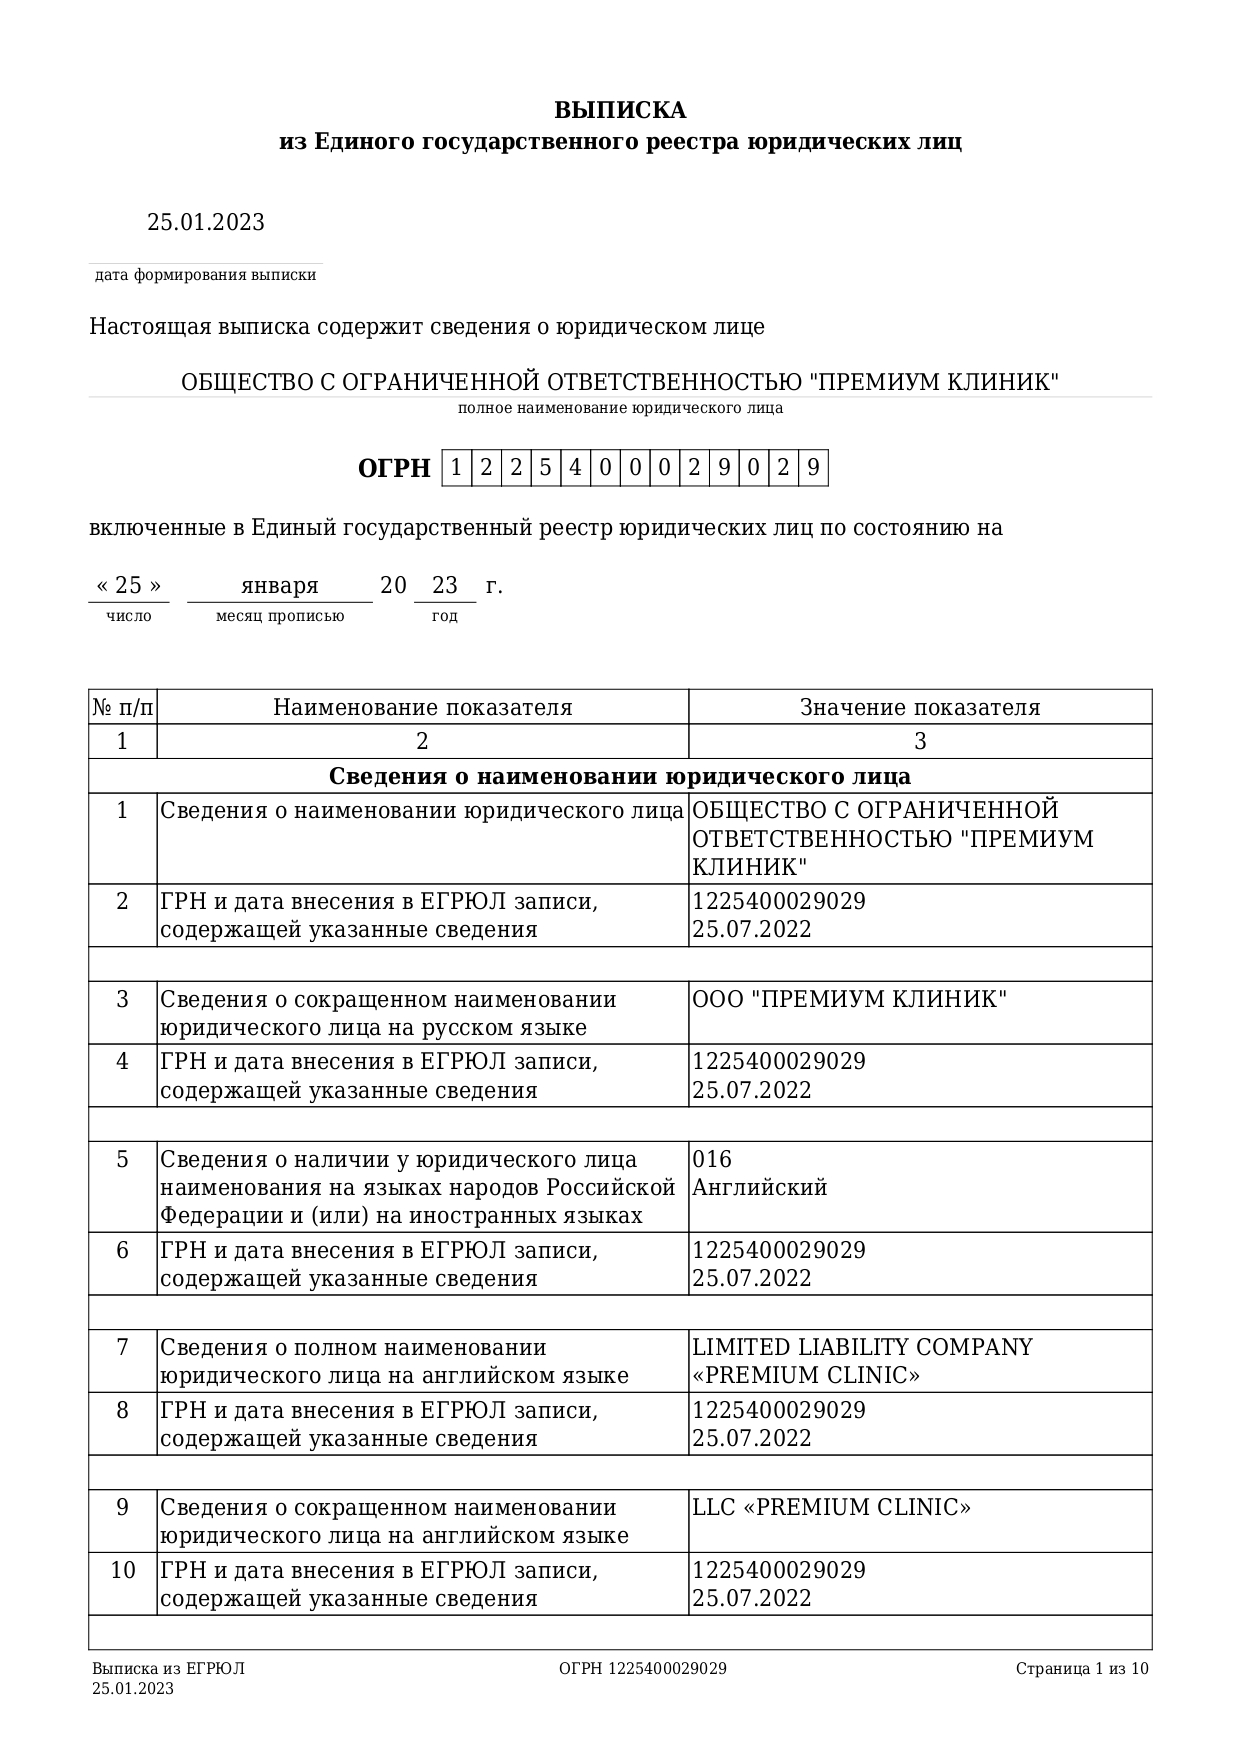

| Вывод из запоя в Кытманово | |

| Basic | 2000₽ |

| Standart | 4000₽ |

| Premium | 6000₽ |

| Капельница от запоя | 1800₽ |

| Капельница от похмелья | 1800₽ |

| Двойная капельница от запоя | 3000₽ |

| Первичная консультация и выезд нарколога на дом | 1500 ₽ |

| Экстренное вытрезвление на дому под наблюдением нарколога | 3000₽ |

| Вывод из запоя в стационаре «Стандарт» (1 сутки) | 5 500 ₽ |

| Вывод из запоя в стационаре «Комфорт / Люкс» (1 сутки) | 8 500 ₽ |

| Выезд нарколога на дом для осмотра и решения о госпитализации | Бесплатно |

| Трансфер в клинику (в Новосибирске) | Бесплатно |

| Продление стационара (каждые сутки) | 4 500 ₽ |

Принимаем к оплате:

* Стоимость вы можете уточнить, позвонив нам или заказав обратный звонок!

Условия рассрочки оговариваются индивидуально при визите в клинику, консультацию можно получить по телефону:

8 (800) 555-14-67